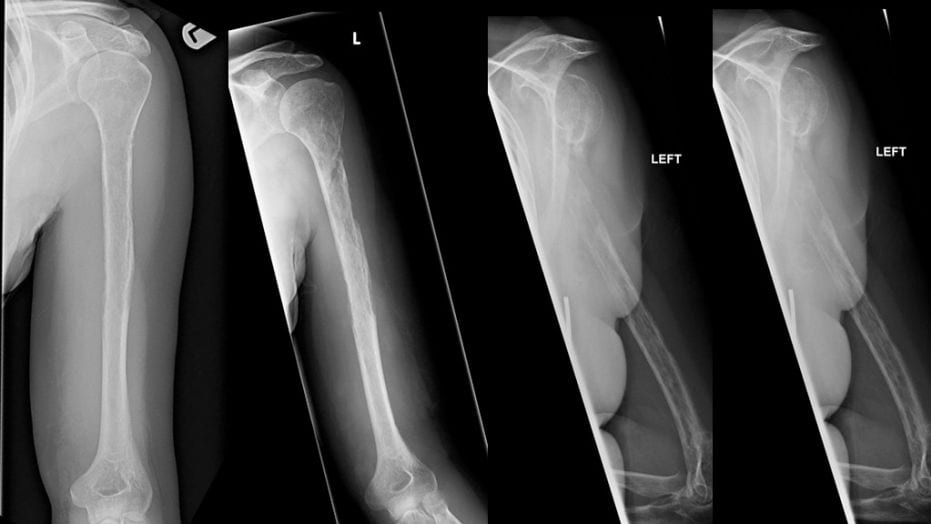

X-rays taken of a woman with so-called “vanishing bone disease” showed her bones gradually passing from sight on the images, according to a Live Science report.

“About 18 months after the woman first went to the doctor, scans revealed her ‘vanishing’ bones; both her humerus and her ulnar bone (one of the two bones in the forearm) appeared to be disappearing on X-rays,” Live Science explained.